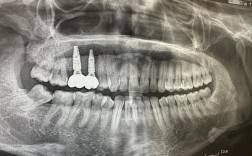

- 主要方法: 外科手术将人工牙根(种植体)植入牙槽骨,待骨结合后安装基台和牙冠。

- 特点: 目前公认的最佳修复方式之一,不损伤邻牙,功能、美观、稳定性最好,但费用最高,治疗周期较长(通常3-6个月),对全身健康和口腔条件有一定要求。